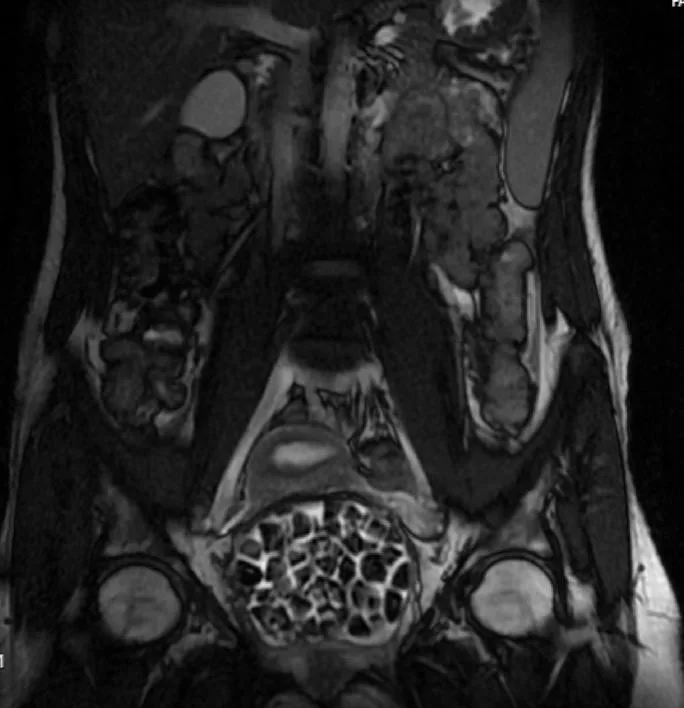

Turkish Doctors Remove 287 Stones From Young Woman

In Türkiye, 21-year-old Fatma Nur Öztürk underwent surgery after severe abdominal pain revealed a rare condition. Doctors discovered and removed 287 stones, the largest measuring 2.5 centimeters, from her bladder and vaginal area.